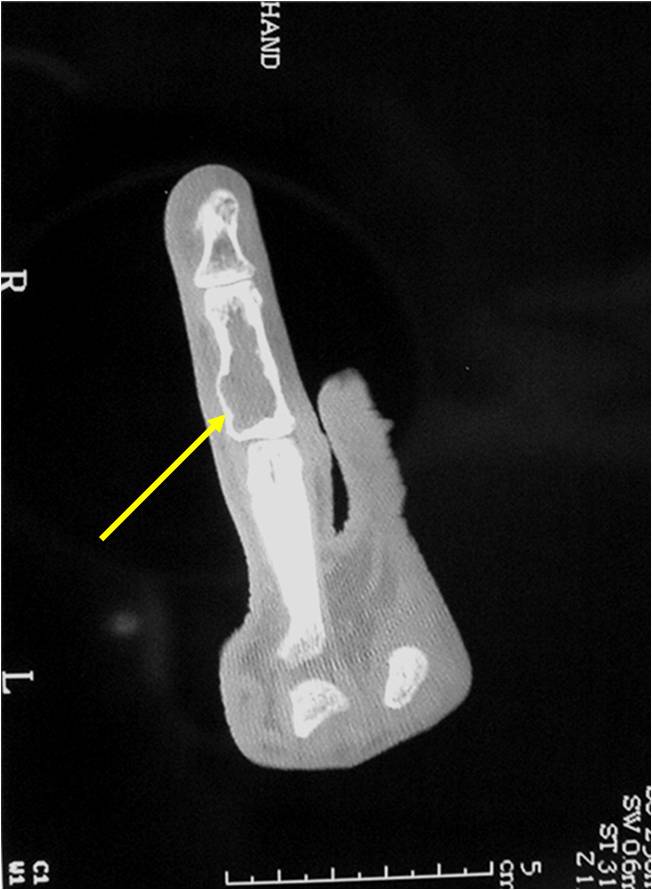

Geographic Lesion Bony Expansion Minimal Calcification Some Enchondromas do not calcify

Geographic lesion, Stippled calcifications in lesion, Phalanx is expanded, Significant endosteal scalloping, No cortical destruction, No soft tissue extension, Cortex Scalloped and Expanded